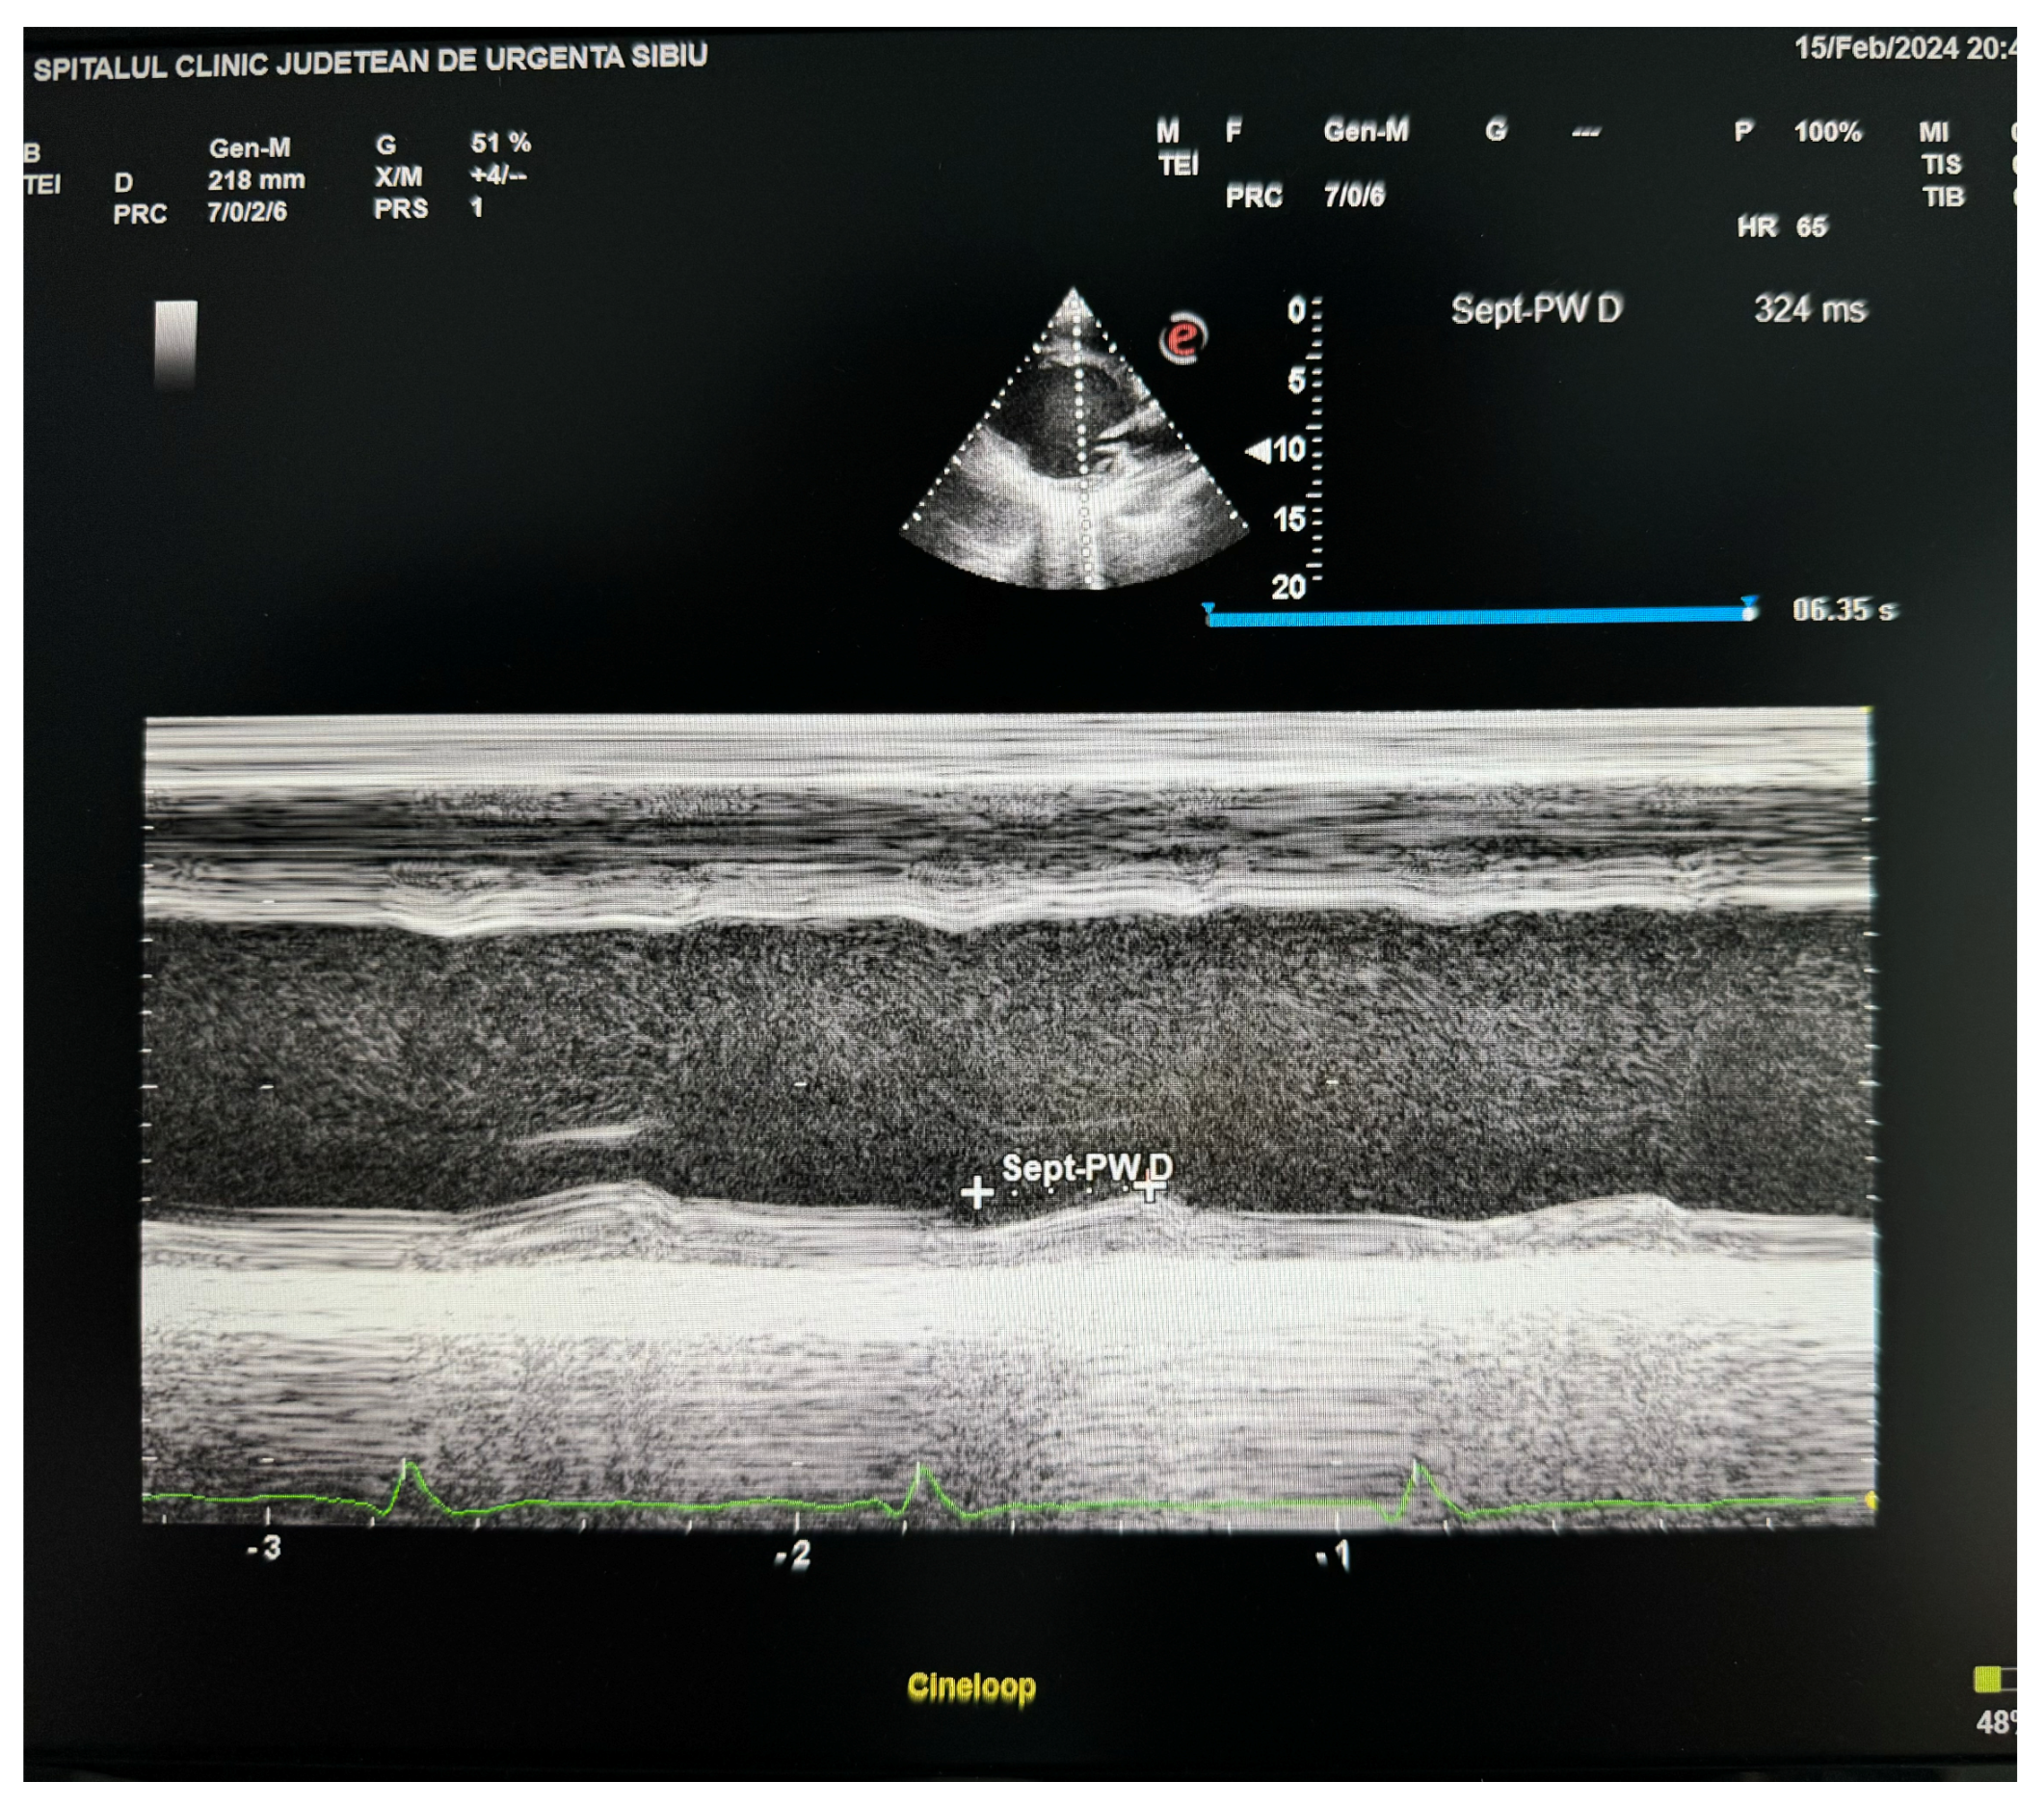

| Septal–posterior wall delay | M mode parasternal LV view | ≥130 msec | Rapid, widely available | More affected by passive motion or tethering; akinesis provides difficulty | |